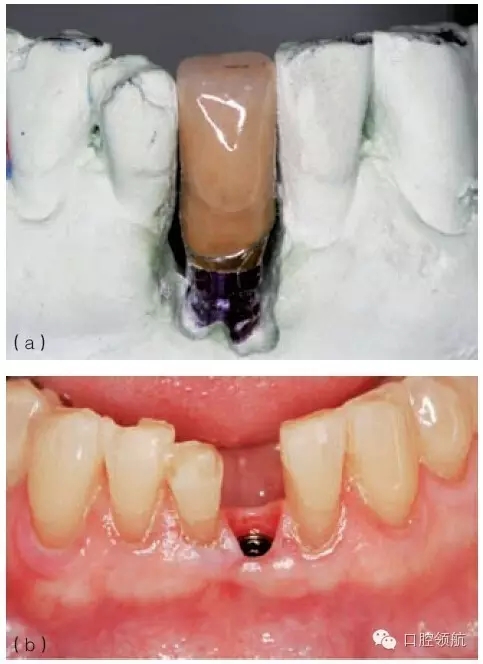

圖9.31 (a)對于深覆患者,當(dāng)種植體植入角度偏頰側(cè)的時候,要相應(yīng)增加植入深度,以避免下頜牙切緣與種植體接觸;增加操作空間,有利于形成逐漸過渡的修復(fù)體穿齦外形。(b)從種植體平臺到修復(fù)體頸部,逐漸過渡的臨時冠軸面外形。(c)臨時冠就位的臨床觀,在美學(xué)區(qū)域,對于非手術(shù)式的組織塑形,推薦2~3個月的塑形時間。